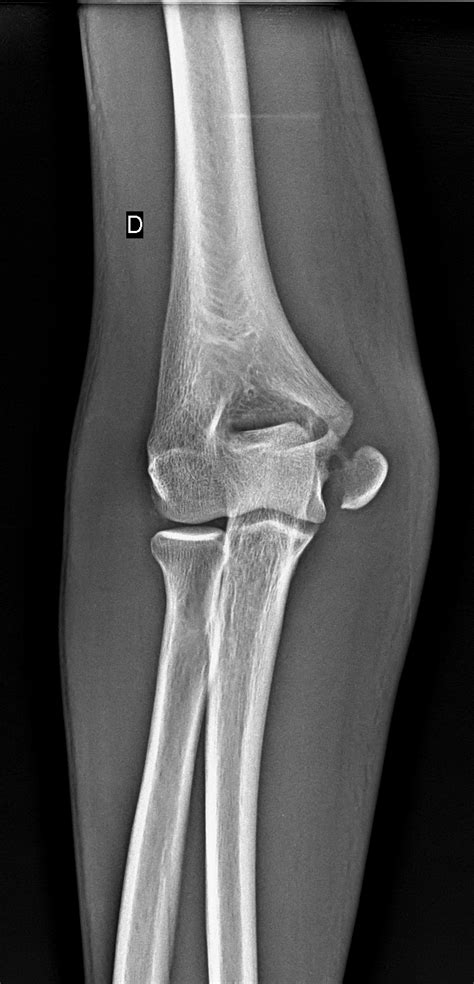

Diagnosing a Medial Epicondyle Fracture

Diagnosing a Medial Epicondyle Fracture involves a combination of physical examination and imaging tests. The diagnostic process typically includes:

• Physical Examination: The healthcare provider will assess the elbow for swelling, tenderness, and range of motion. They may also check for any deformities or instability in the joint.

• Imaging Tests: X-rays are the primary imaging tool used to diagnose a Medial Epicondyle Fracture. They can reveal the location and extent of the fracture. In some cases, additional imaging such as a CT scan or MRI may be required to provide a more detailed view of the injury.

Accurate diagnosis is crucial for determining the appropriate treatment plan.